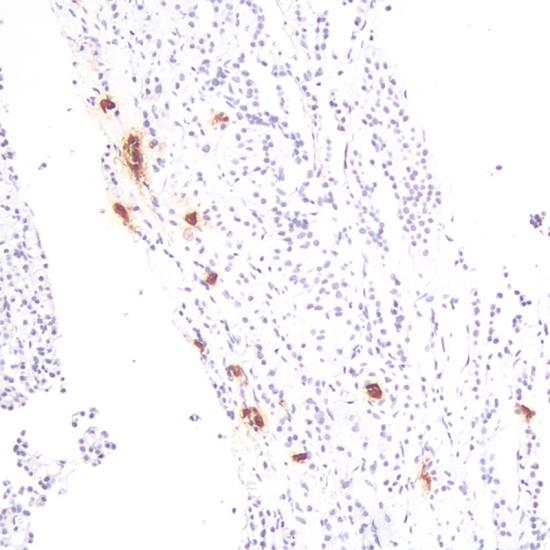

Human Growth Hormone抗體試劑(免疫組織化學) 閩廈械備20180231號

• 陽性部位:

細胞漿

• 陽性對照:

垂體腺瘤

生長激素(GH)是由垂體前葉生長激素細胞合成和分泌的一種激素,可以促進蛋白質合成,促進骨骼發(fā)育。此抗體可以與人的GH反應,與催乳素、TSH、LH、FSH等激素有微弱的交叉反應,主要用于垂體腺瘤功能性分類的研究。